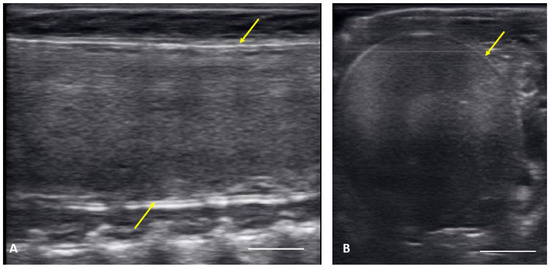

| Previtellogenic Follicles (PVF) | Anechoic Follicles, Small and Rounded, String-Aligned |

|---|---|